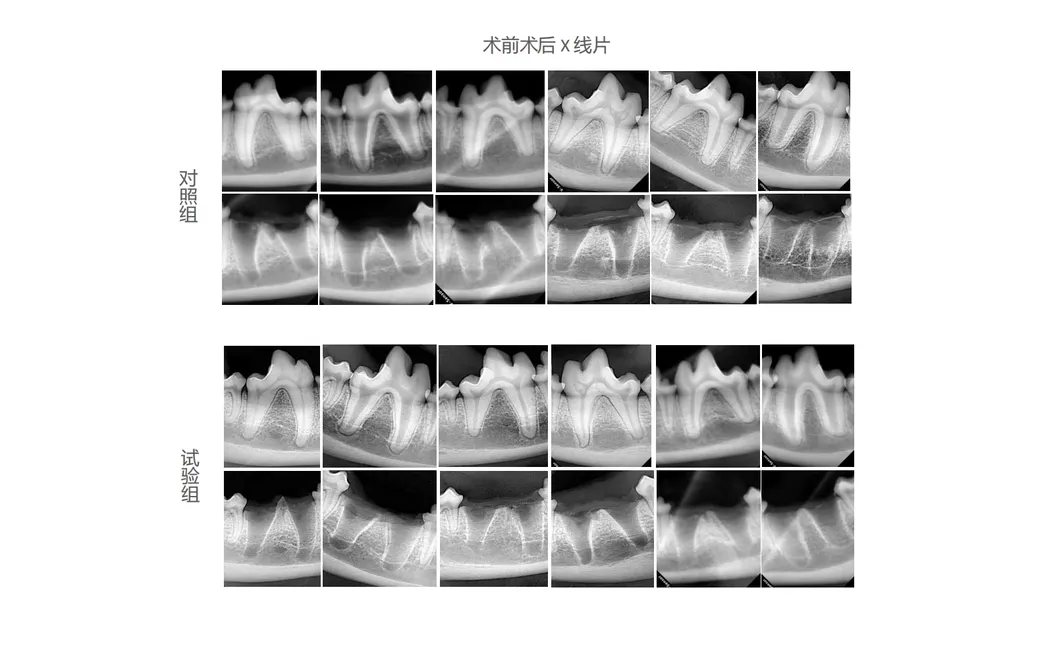

In this groundbreaking study, subjects were meticulously chosen to analyze the effectiveness of next-generation dental tools. The study compared traditional manual extraction devices against the revolutionary Pneumatic Dental Elevator Kit. Researchers documented physiological parameters, intraoperative complications, extraction duration, and socket damage, as well as postoperative healing through haematological and histological evaluations.